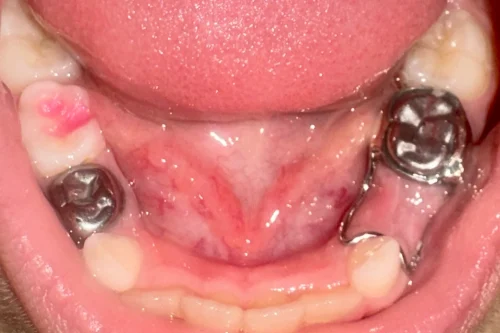

The band and loop appliance was custom-fabricated in the lab. The stainless steel loop was contoured during the second visit to fit the edentulous space. Then it was soldered to the band & smoothed. The appliance was tried, fitted, and cemented with the help of glass ionomer cement.

The entire process took about 30 minutes across two appointments. The child remained comfortable throughout.